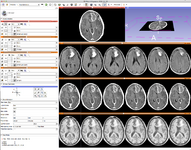

The community of Slicer developers is proud to announce the release of Slicer 4.0.

- Slicer 4.0 includes a major overhaul of the user interface, improved and simplified workflows for major tasks, simplified procedures for developers, and improved Python support.

Slicer is a community platform created for the purpose of subject specific image analysis and visualization.

- Multi-modality imaging including, MRI, CT, US, nuclear medicine, and microscopy

- Slicer 4.0 - New and Improved Modules